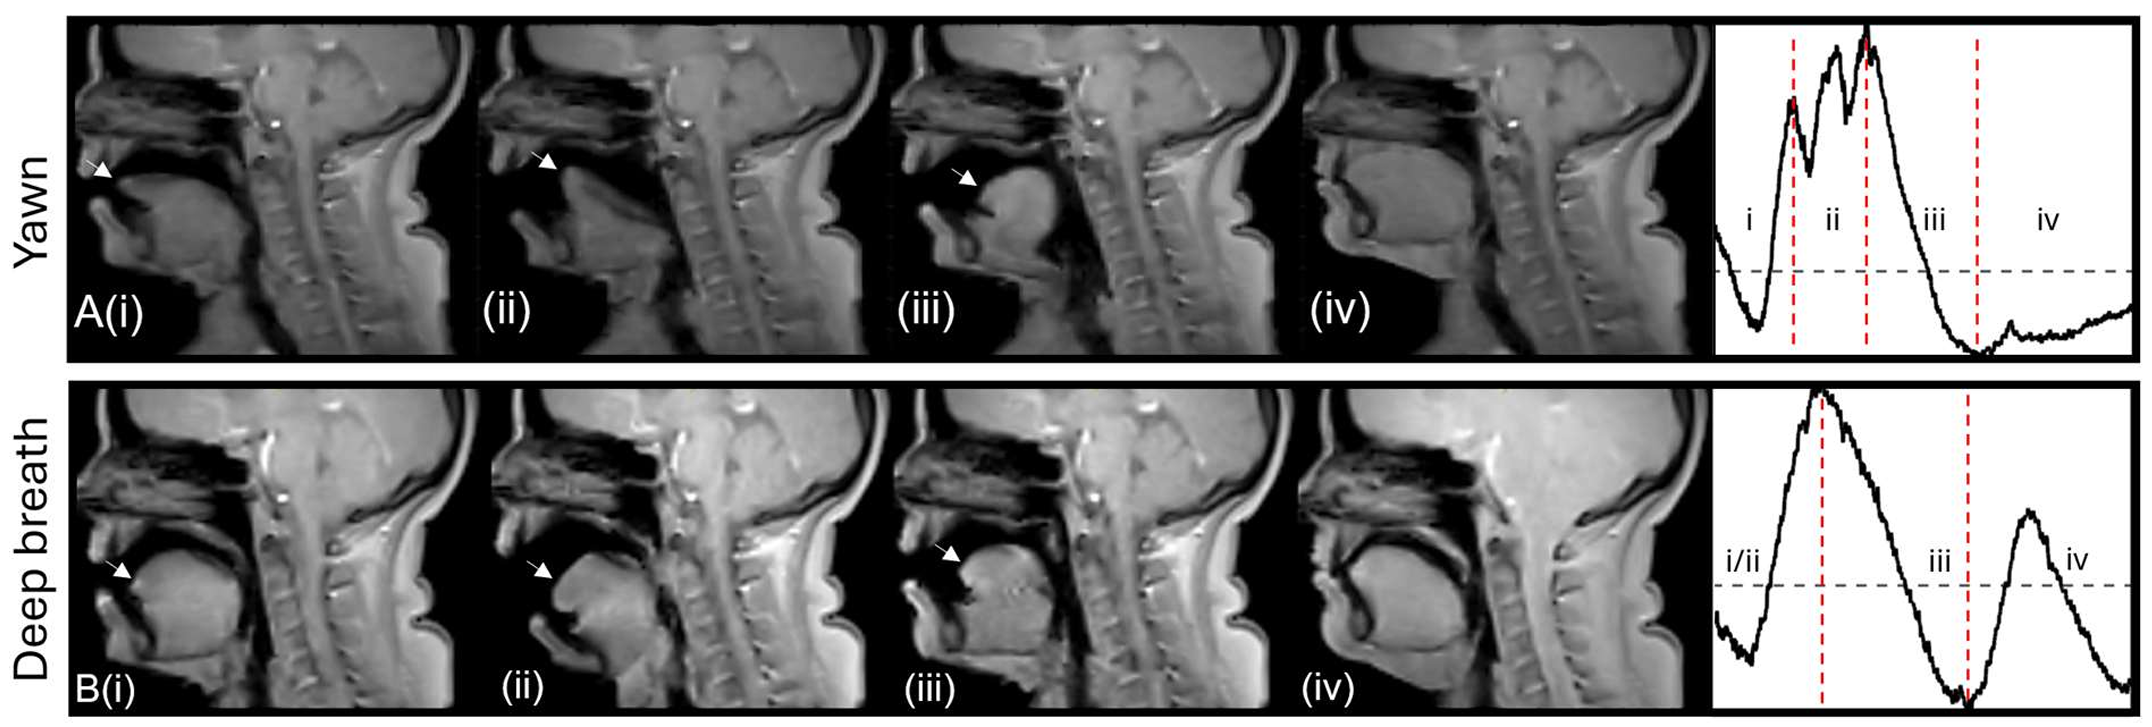

“The yawn seems to be creating a flow of CSF away from the brain, whereas taking a deep breath causes a flow of CSF towards the brain,” Martinac claimed. “This was an unexpected finding for us.” Cerebrospinal fluid (CSF) surrounds and cushions the brain and spinal cord, as well as providing nutrients to the nervous system and assisting with the removal of waste. When someone takes a deep breath, their cerebrospinal fluid moves towards the brain. However, the fluid moves away from the brain while yawning.

The change in blood flow and pressure during yawning and taking a deep breath is also evident in the images. During yawning, there was an increase in blood flowing from the brain through the veins in the neck, creating space for fresh blood to enter the brain through the arteries.

Blood flow does not reverse direction when yawning, but during the initial phase of a yawn, the blood flow into the brain through the carotid arteries increases by 30%. Such an increase in blood flow into the brain during yawning indicates that yawning has a greater effect on circulation than just one factor.

Finally, the research team noted that each participant had his or her own unique yawning style. Each person’s motion of his or her jaw and tongue was consistent each time he or she yawned. Even when the participant attempted to hold back the yawn, the same pattern of motion was observed. This suggests that yawning is controlled by inherent wiring in the brain rather than learned behaviour.

Research has shown that yawning patterns vary between individuals. However, each person tends to display a consistent yawning pattern over time. Yawning’s function is a mystery to many researchers, and they have put forth various hypotheses about why we yawn. The researchers have provided a new possibility that yawning may also be one method to move fluids around for optimal brain health.